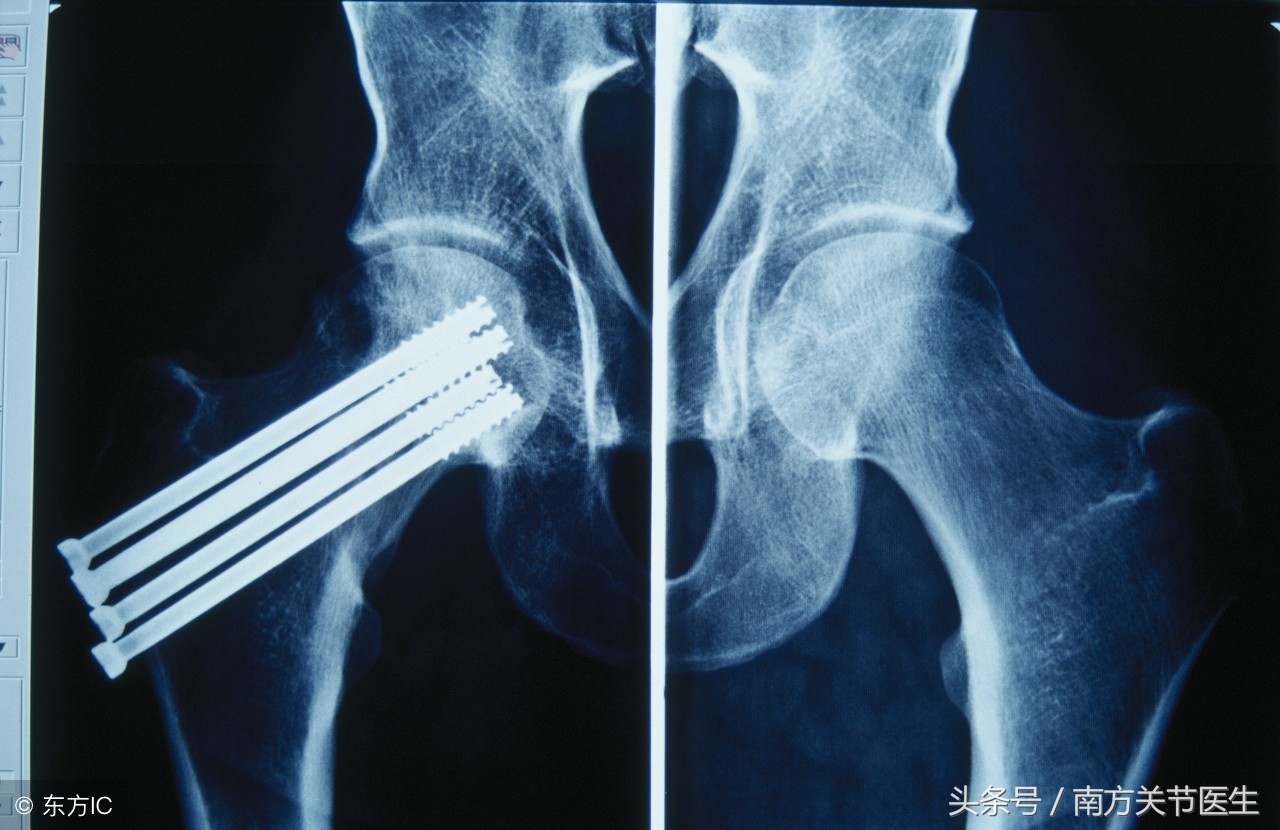

空心钉固定:对于无移位型且骨折处仅有裂缝或完全骨折当折端嵌插的患者,该治疗方法更加受用。以空心钉固定可保证骨折处不发生移位,日常的护理及活动较方便,且无需长期服用接骨药。